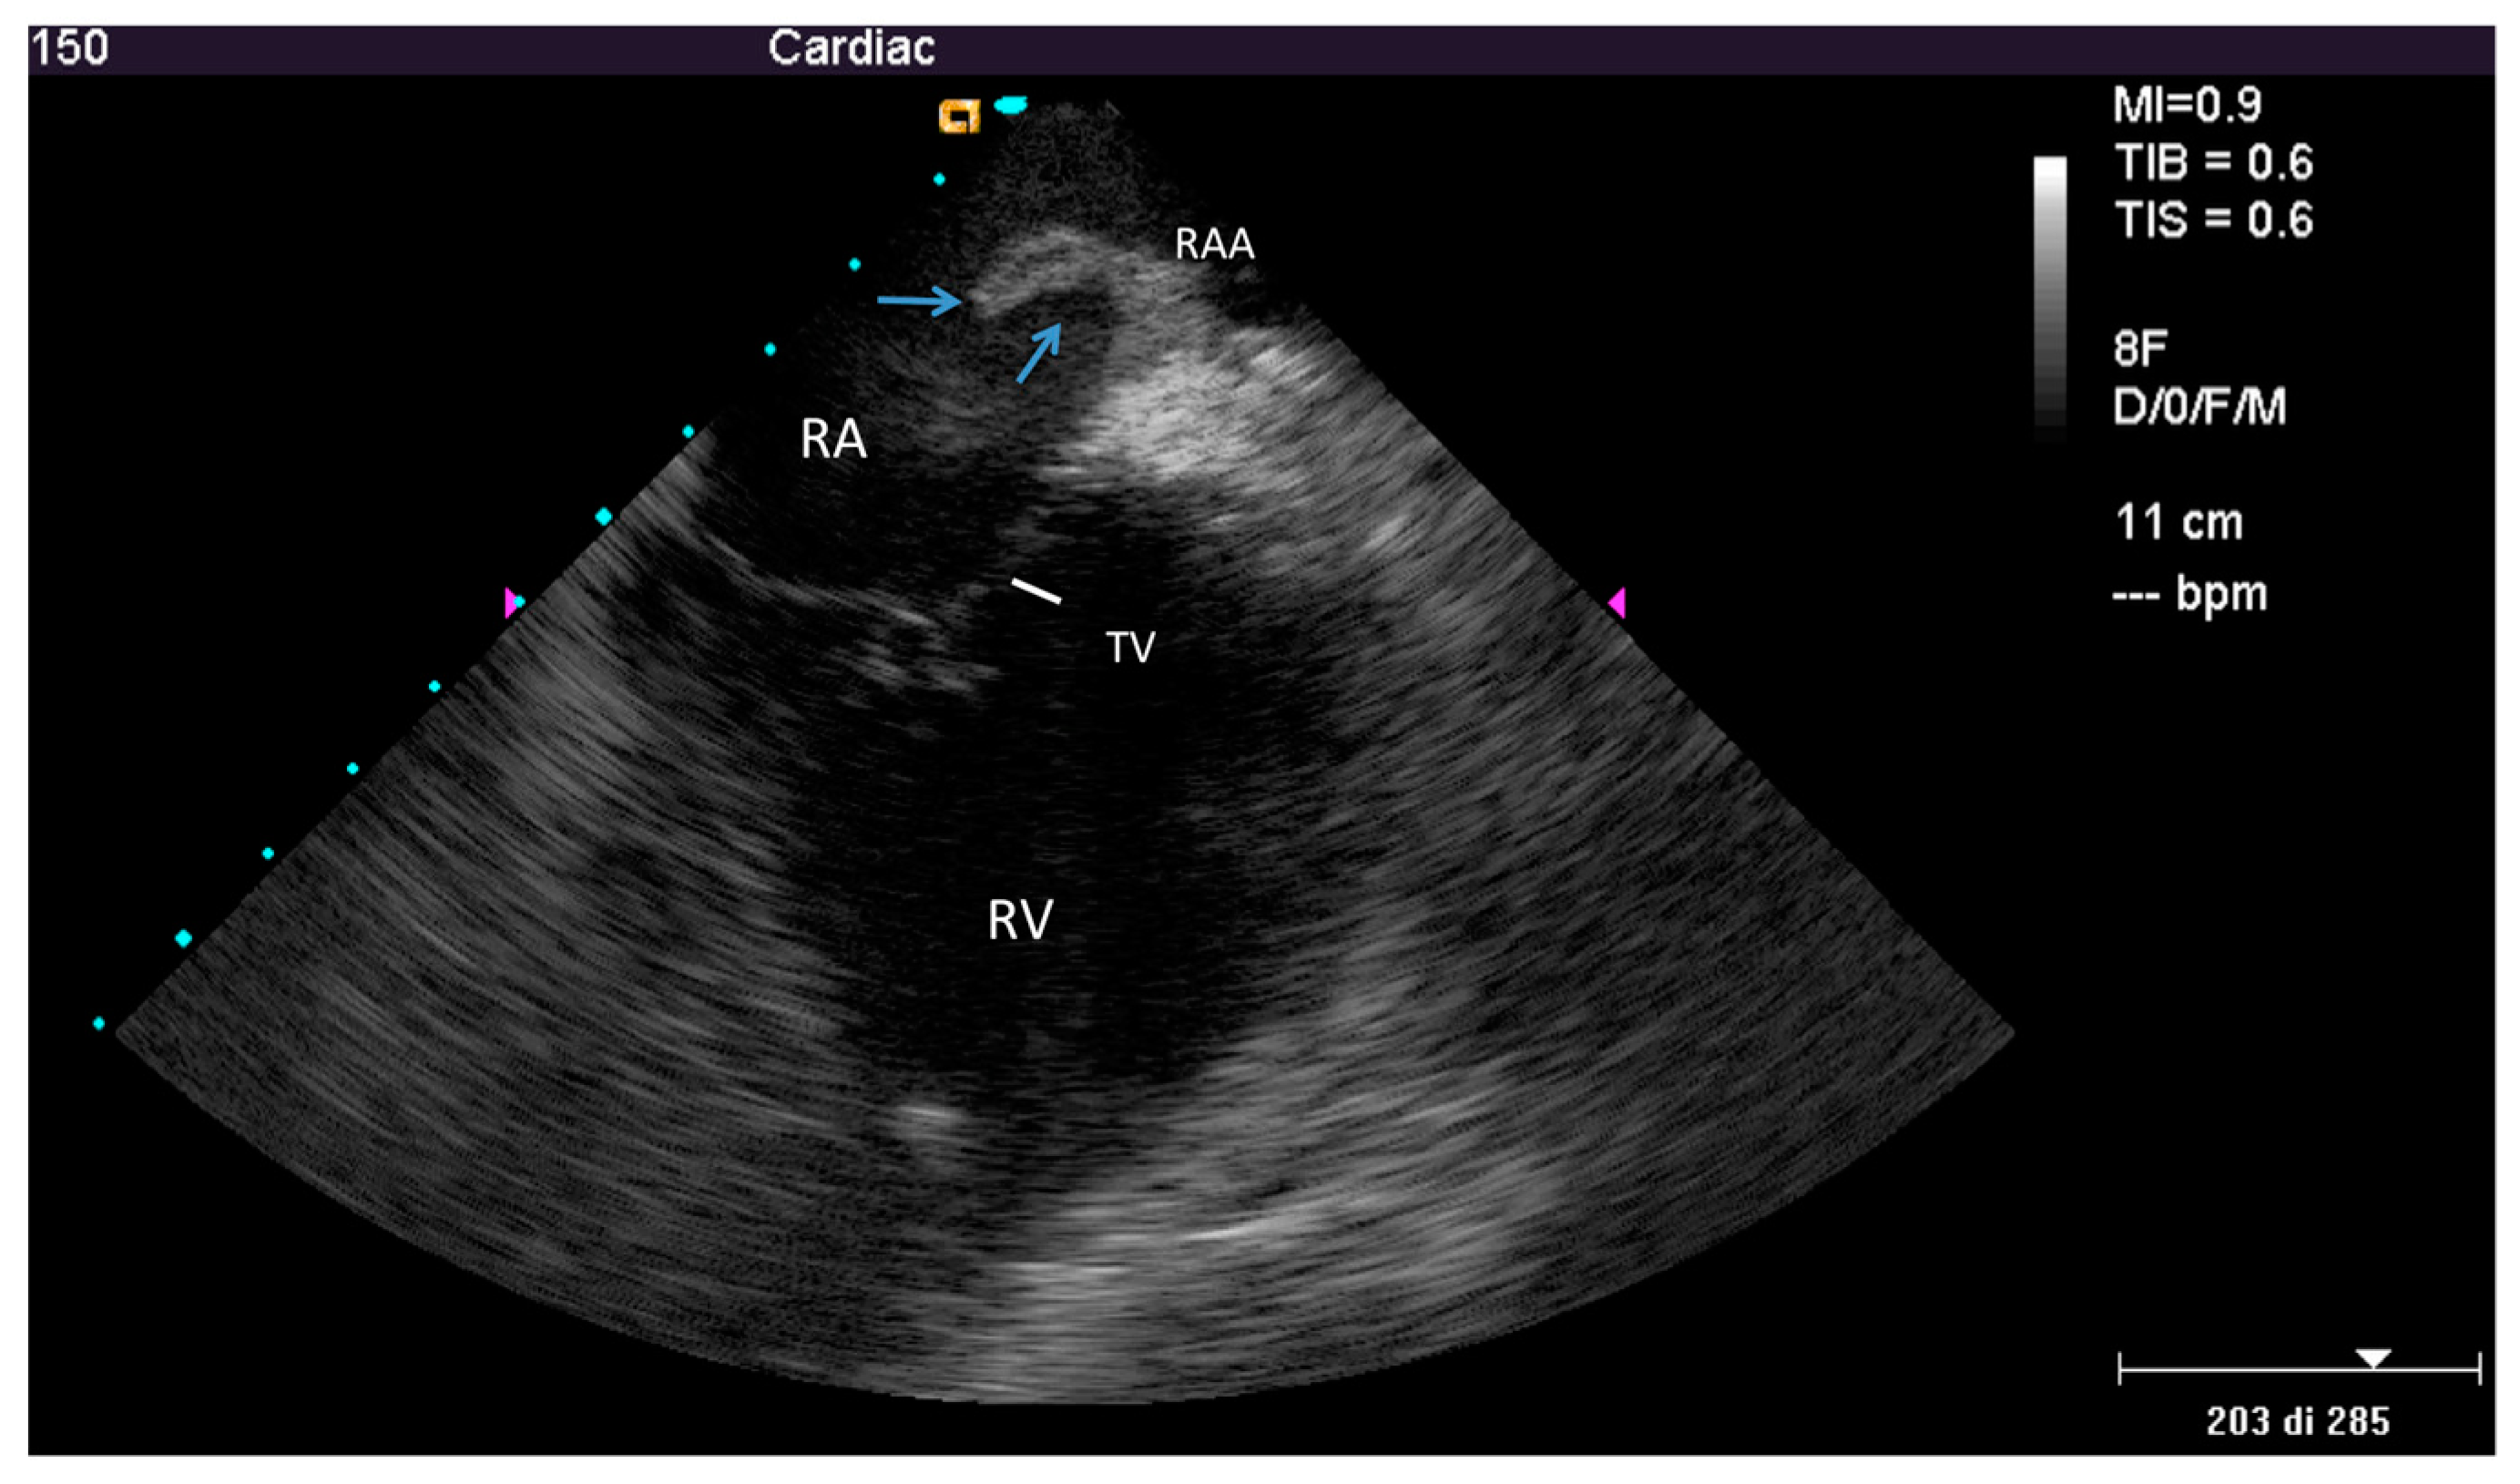

2.2.1. Before Extraction

3.1. Pre-extraction